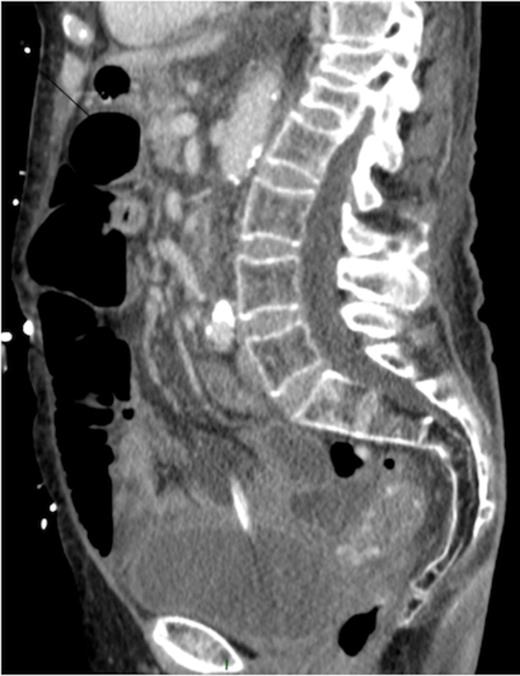

Thoraco-abdomino-pelvic CT scan was then performed. The pelvic sagittal scan showed the Foley catheter perforated the urinary bladder and liquid effusion likely to be urine (Figure 1). The Foley catheter was unfortunately withdrawn to be well replaced.

Sagittal CT image showing urethral catheter in the abdominal cavity.